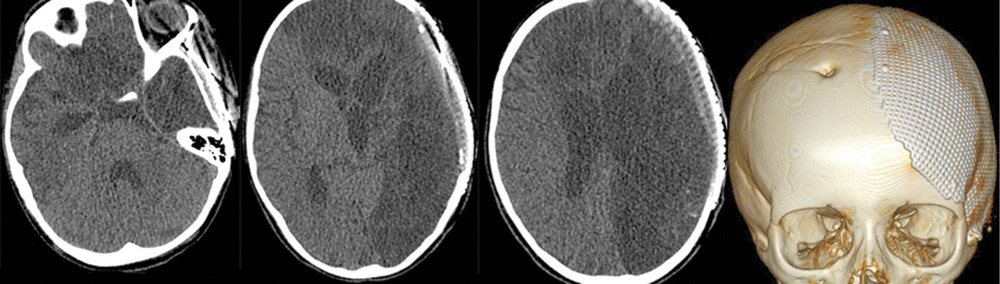

На 28-е сутки после аСАК отмечено выполнение простых инструкций, и пациентка была переведена на спонтанное дыхание через трахеостомическую трубку. При К.Т. в левом полушарии головного мозга отмечались выраженные постишемические нарушения. Гидроцефалии на фоне ВПШ не было (рис. 5).

Через несколько месяцев в другом нейрохирургическом стационаре проведены краниопластика в левой лобно-теменно-височной области и удаление ВПШ в связи с его дисфункцией.

Через 2 года после аСАК, несмотря на выраженные кистозно-глиозные изменения в левом полушарии (рис. 6),

девочка практически не имеет ограничений в повседневной двигательной активности, самостоятельно ходит, разговаривает, посещает школу. Из очаговой неврологической симптоматики сохраняется правосторонний гемипарез до 4 баллов. К настоящему времени состояние пациентки соответствует ШИГ IV.